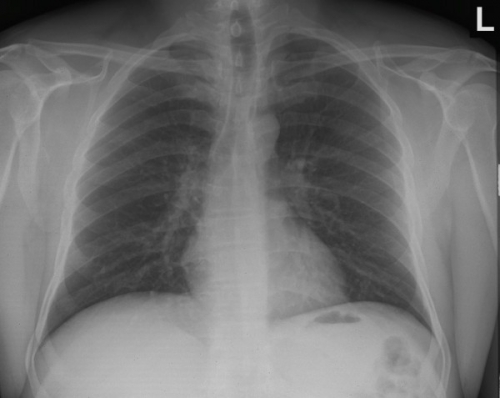

Tool to train medical student's eyes as to what a normal chest x-ray looks like, with over 500 consecutive normal images.